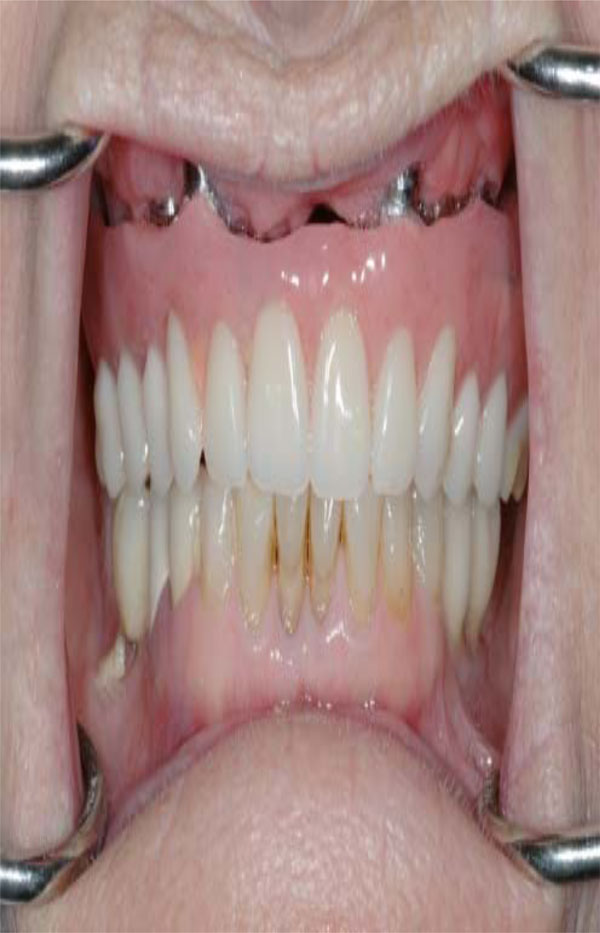

Intaglio surface of maxillary hybrid has been custom designed in order to improve esthetics and phonetics.

Esthetic demands tend to be more dramatic with maxillary prostheses than mandibular prostheses (Fig. 3). As per Zarb and Schmitt, unlike mandibular implant prostheses were hygienic type designs have proven to be functionally and esthetically acceptable, maxillary implant prostheses demand different sized and shaped labial/buccal flanges that may or may not compensate for optimal esthetics, phonetics, and masticatory function (Fig. 4). Additionally prosthetic gingival tissues are often required due to resorptive patterns of edentulous maxillae. Resorptive patterns in maxillae are dissimilar to mandibular resorption pattern: maxillae resorb superiorly, posteriorly, and medially: mandible resorbs inferiorly, anteriorly, and laterally [26, 27].